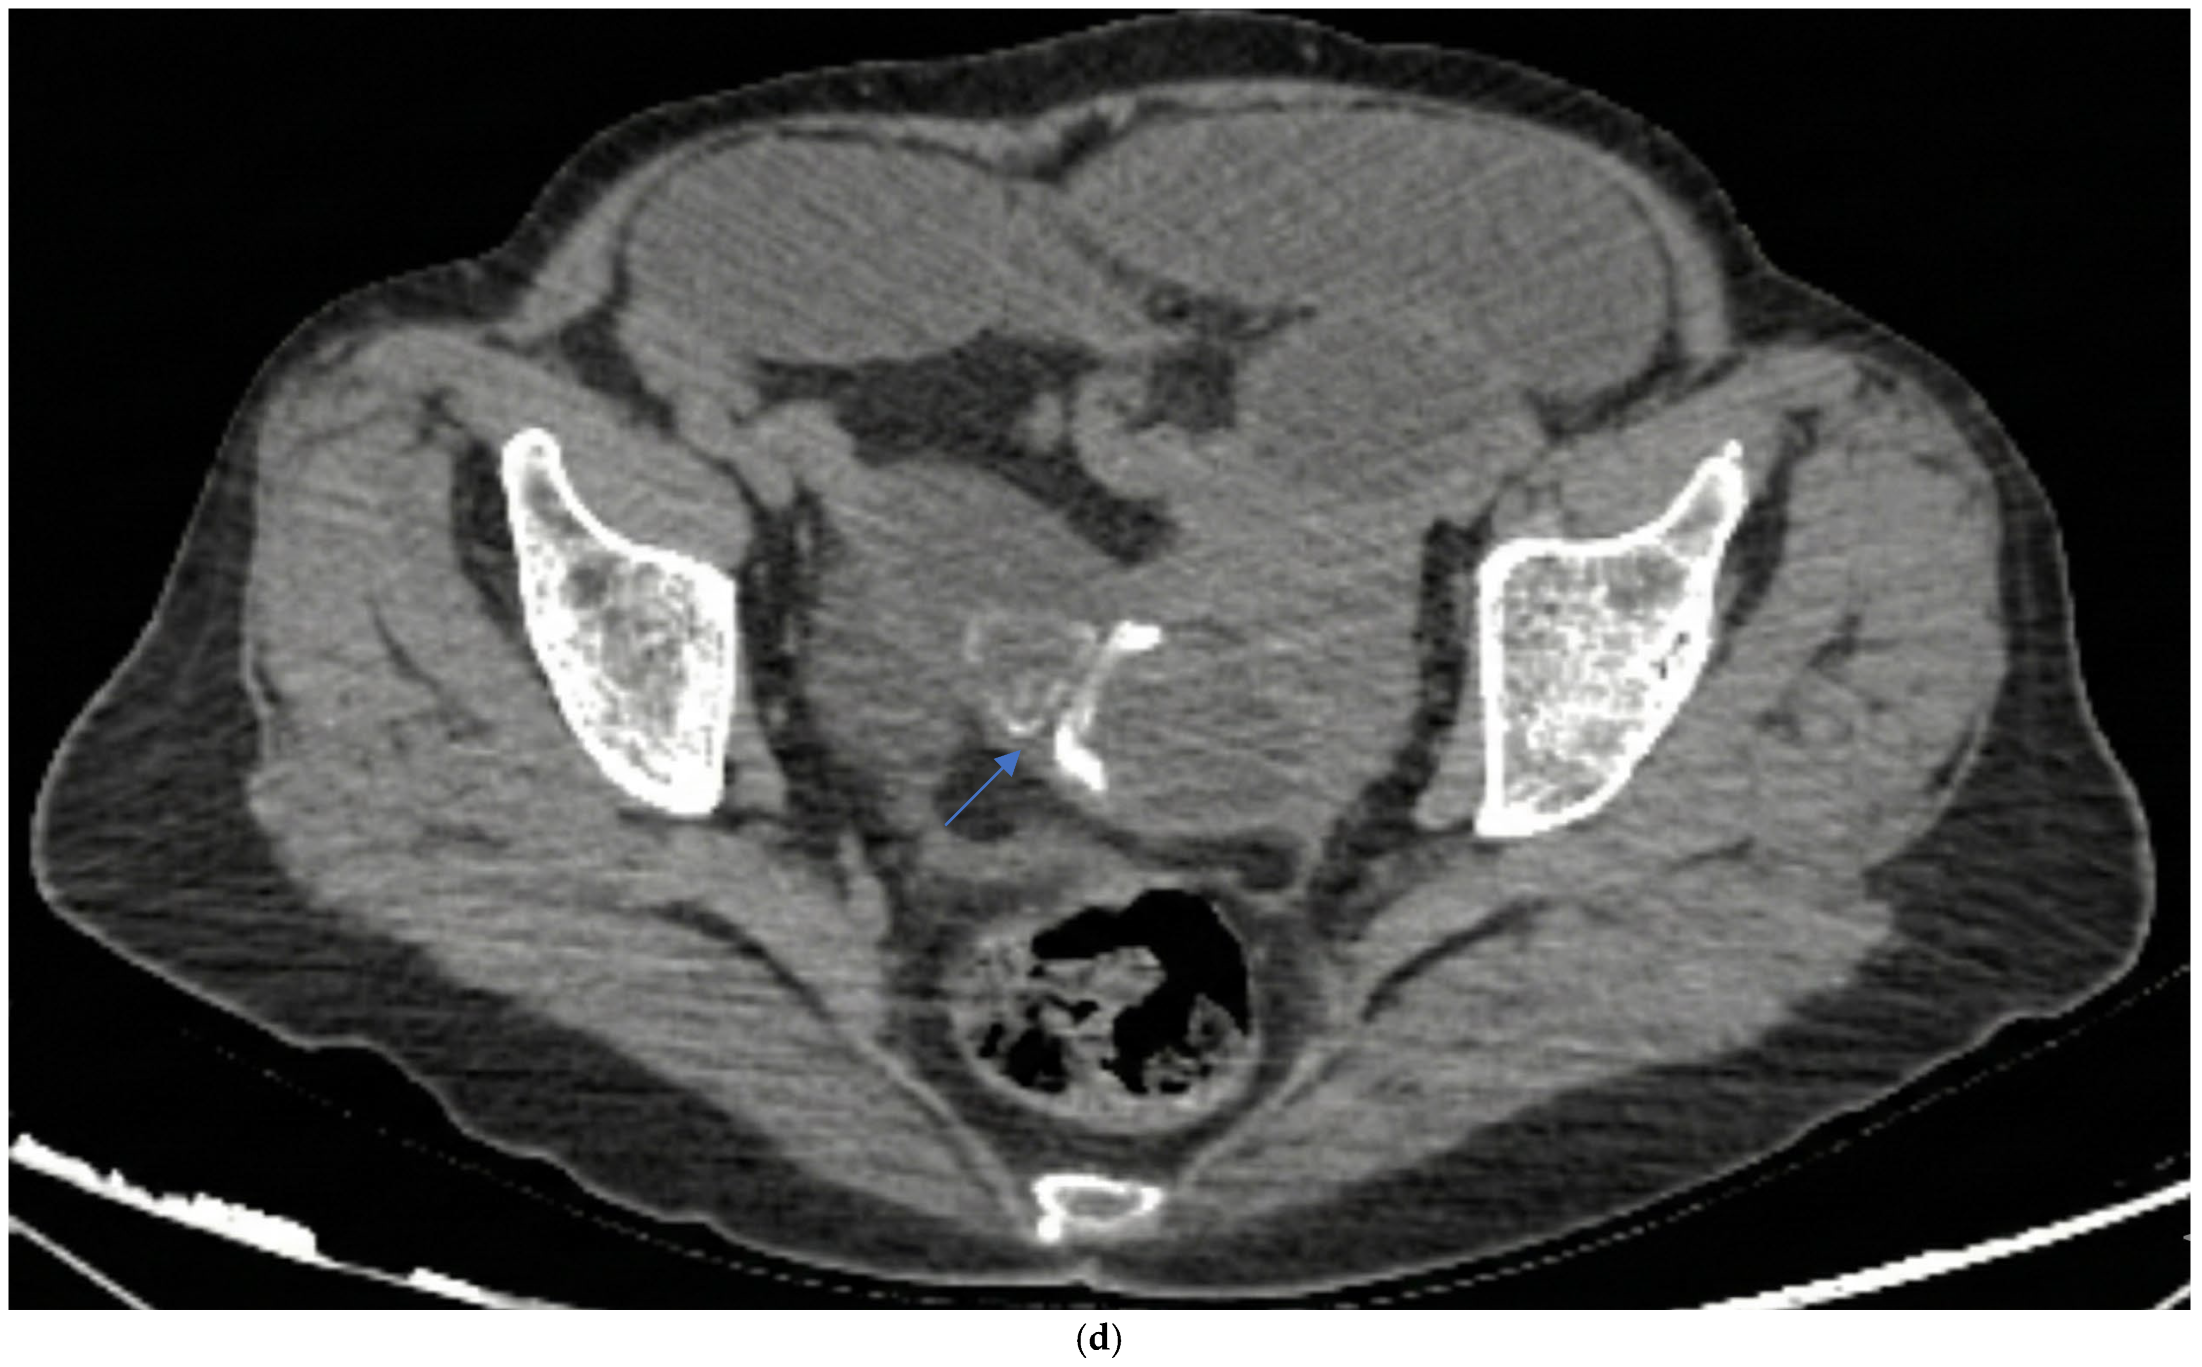

Preoperative imaging confirmed GI in all patients (Table 2). All patients had CT and plain X-ray, but none had a preoperative USG in the emergency department. CT revealed a bilioenteric fistula in all cases (12/12) (Figure 3b) and Rigler’s triad in 11/12 patients (91.7%). Air-fluid level and small bowel dilatation > 3 cm were seen in 11/12 patients (91.7%) (Figure 3c); one patient had stone impaction in the duodenum and did not show an air-fluid level. Free fluid was present in 4/12 patients (33.3%), suggesting potential peritonitis. The mean number of stones was 1.6 ± 1.2 (range 1–4), with a mean stone size of 3.19 ± 0.6 cm (range 2.6–5). The stones were primarily located in the distal ileum in 8/12 patients (66.7%) (Figure 3d). Plain X-ray showed an air-fluid level in 11/12 patients (91.7%) and pneumobilia in 2/12 patients (16.7%) (Figure 3a). Previous abdominal surgeries were found in 5/12 patients (41.67%).

Figure 3.

Radiologic images (a) plain X-ray air fluid level and pneumobilia (arrow). (b) Ct-scan bilioenteric fistula and stone (arrow). (c) ileus. (d) terminal ileum gallstone (arrow).

In our study, all 12 patients underwent CT, and Rigler’s triad was identified in 91.7% of patients, a rate substantially higher than the traditionally reported rates, reflecting CT’s superior sensitivity compared to X-ray. Small bowel dilatation exceeding 3 cm and air-fluid levels were seen in 91.7% of patients (n = 11/12); one patient with duodenal stone impaction did not show an air-fluid level. In our series, 66.7% of stones were located in the distal ileum, consistent with the literature. Only one patient had a stone impacted in the duodenum, representing Bouveret’s syndrome, which accounts for less than 10% of GI cases [4]. None of our patients underwent preoperative USG, which aligns with current practice favoring CT in emergency presentations.